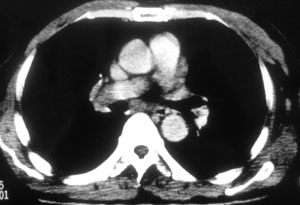

性别 男  62岁 因咳嗽及左肱骨剧烈痛疼数天来院检查。

右中央型肺癌并肱骨转移。

考虑右肺中叶肺癌并左肱骨转移伴病理性骨折。

支持右肺中心型肺癌并肺内及左肱骨转移伴病理性骨折

右肺中心型肺癌并中叶不张,左肱骨溶骨性转移并病理骨折。